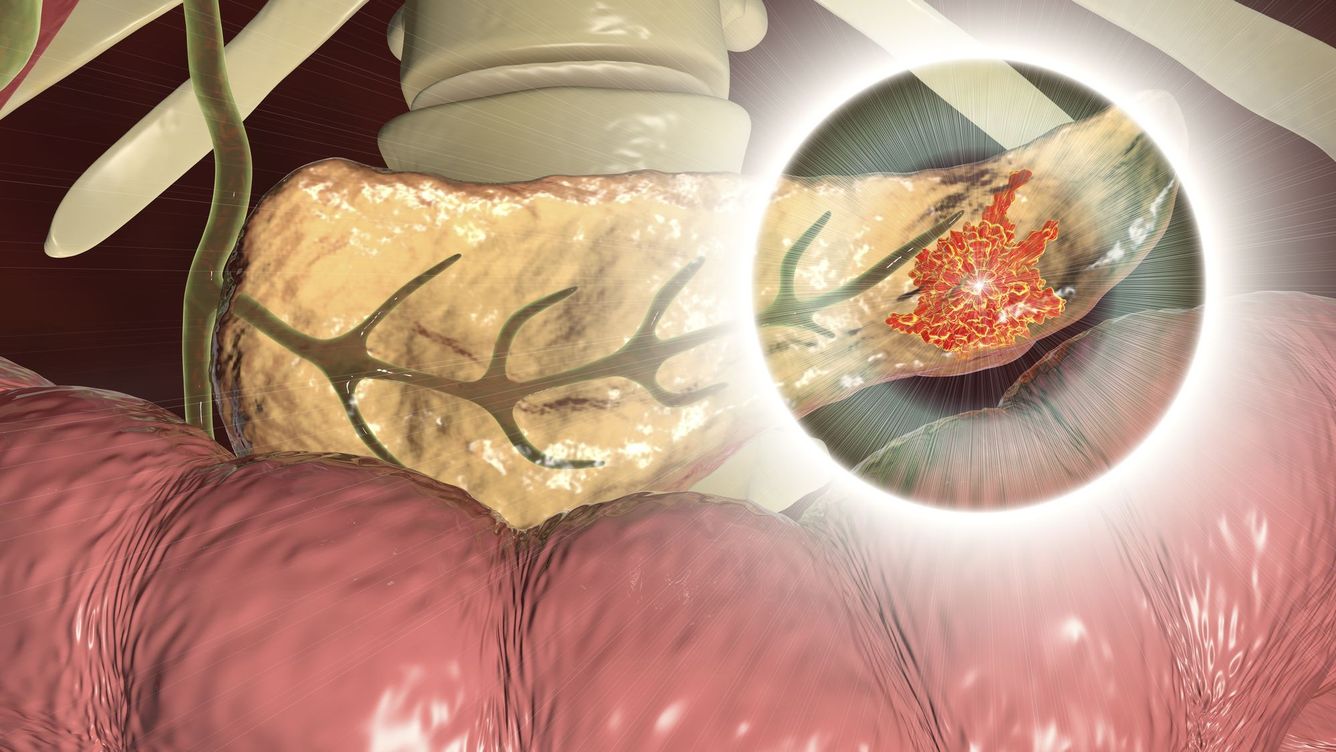

🔬 Molekyl kan bota cancer i bukspottskörteln på 14 dagar

Molekylen PJ34 gör att cancerceller dör när de delar sig. I försök på råttor var 90% av cancercellerna borta en månad efter avslutad behandling.